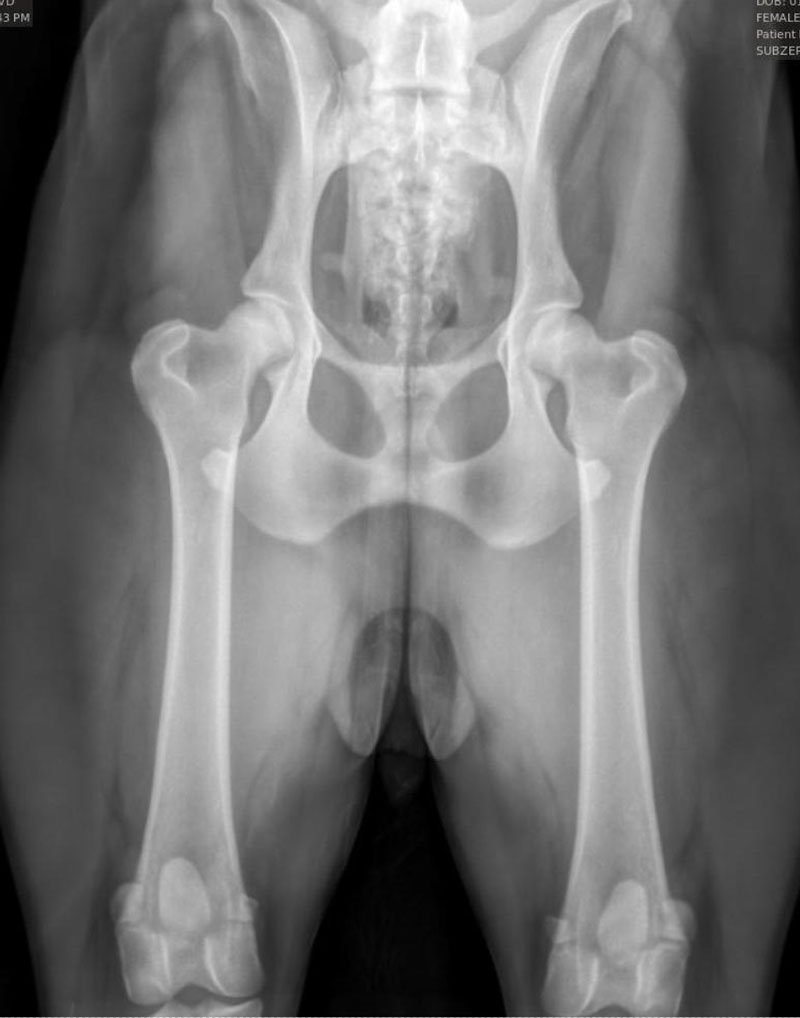

We are also proud to offer OFA (Orthopedic Foundation for Animals) image submissions. This is a requirement amongst many AKC breed clubs and may include several different image types such as:

We frequently receive inquiries regarding our success with proper positioning for OFA images, specifically for hips. Translating this success can be challenging, so we have included images of various breeds that we have taken. We take great pride in our success with these images and many others like them. As extreme perfectionists, we appreciate owners who understand that we strive for the best technique and outcome while minimizing stress and ensuring the comfort of your dog(s), particularly since all images taken here are done WITHOUT sedation.